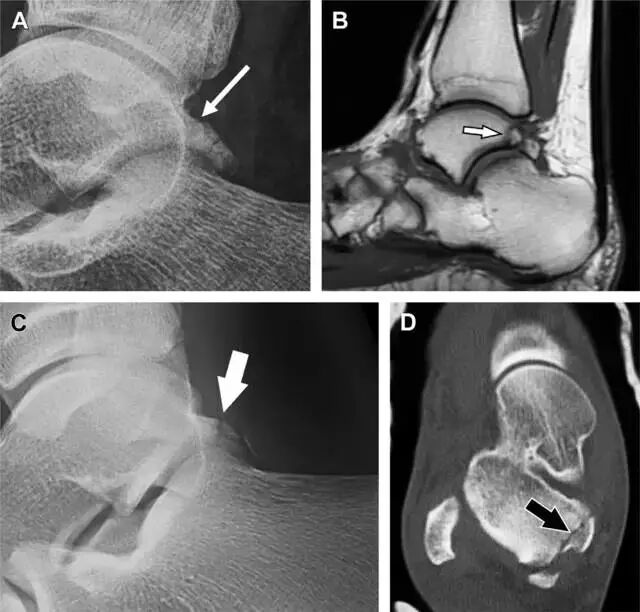

19距骨后突骨折

距骨后突有内侧结节和外侧结节,距骨后突内侧结节撕脱性骨折常发生在背屈内旋的暴力作用下。严重跖屈时,胫骨后缘和跟骨挤压距骨后突外侧结节呈楔形,易发生粉碎性骨折。这些骨折细微且需与三角骨鉴别。侧位片观察距骨后突骨折最佳,常规拍片很难发现,当高度怀疑这种骨折又没法做 CT 时,建议加做多个角度的外旋斜位片(图 5)。

图 5 距骨后突骨折。侧位片(A)和 MRI 矢状位 T1 加权像(B)均示后外侧突的简单骨折(箭头),再次阅片时才发现 X 线片上的骨折;侧位片(C)和 CT 横断面图像示后内侧突的粉碎型骨折(箭头)